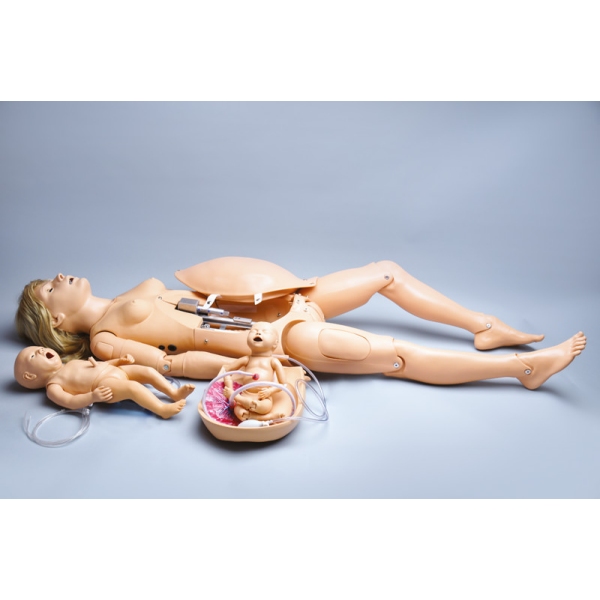

Noelle Simulator poroda mater in novorojenčkov

Zasnovan tako, da zagotavlja popolno porodno izkušnjo pred, med in po porodu.

Simulator ima naslednje funkcije:

- artikulacijska ženska lutka polne velikosti

- intubabilna dihalna pot z dvigom prsnega koša

- roka za intravenozno infuzijo za zdravila/tekočine

- odstranljivo pokrivalo za trebuh

- vadba Leopoldovih manevrov

- številni srčni zvoki ploda

- avtomatski porodni sistem

- merjenje spuščanja glave in razširitve materničnega vratu

- več lokacij posteljice

- zamenljivi dilatacijski pripomočki

- en premikajoč se porodni otrok s posteljico

- en reanimacijski otrok z intubabilno dihalno potjo in mestom za popkovnični kateter

Teža: 48 kg